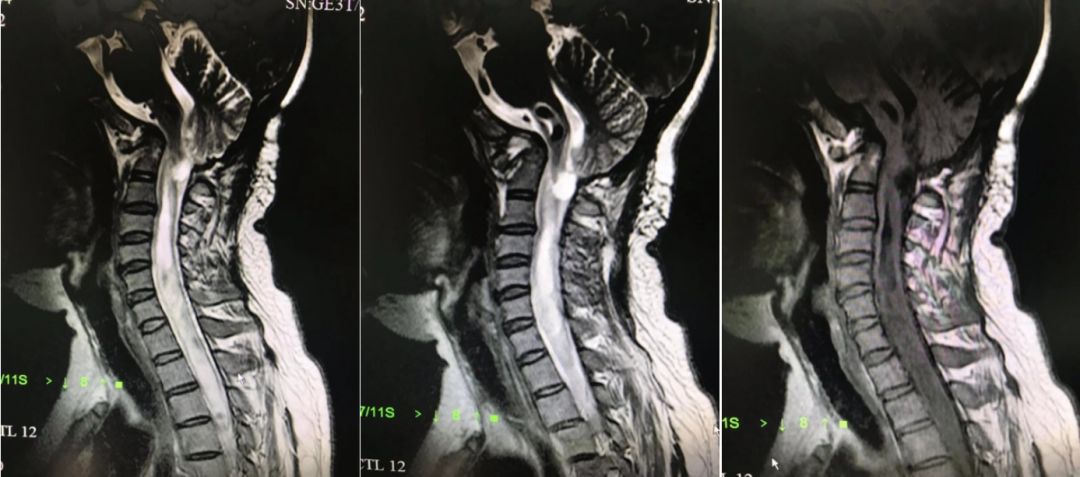

外院寰枕减压术前MRI影像,可见颅底凹陷,小脑扁桃体下疝畸形,脊髓空洞症。

外院术后七个月复查MRI,提示寰枕减压术后,小脑下垂,颅底凹陷仍然存在,小脑扁桃体 切除后表现,局部有粘连,同时脊髓空洞较前明显增加。

术后复查MRI,提示脊髓空洞明显改善。